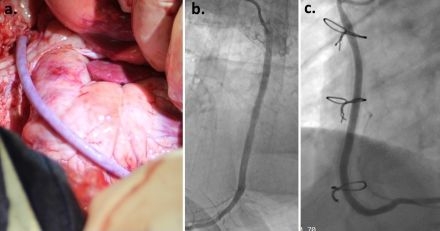

Methods: In the preclinical phase, 4mm diameter ATEVs were implanted as coronary bypasses in 22 ovine. ATEV Gen 1 (n=13) without ESS; and Gen 2 (n=9) with ESS were implanted for duration up to 18 months. Follow-up included serial angiography, histopathology, and mechanical testing. With preclinical safety data, a clinical first-in-human feasibility study (VCAB-1, NCT06434935) enrolled three patients with multivessel disease receiving ATEV with ESS as a secondary bypass conduit.

Results: Gen 1 ATEV without ESS experienced 31% (4/13) kink-related thrombotic events. Gen 2 ATEV with ESS achieved 100% patency in all animals surviving perioperative complications (n=5). Planned explants at 180 days (n=3) and on-going (555 days) maintained TIMI-3 flow. Histopathology revealed progressive remodeling with endothelialization, cellular infiltration, and elastic lamina formation without inflammatory response or calcification. Explanted conduits maintained burst pressures (2100-4200 mmHg) exceeding native vessels. In the clinical study, two patients enrolled were successfully implanted with triple bypass which include LIMA to LAD, ATEV and SVG as other the two bypass. No suture hole or conduit wall bleeding was observed for the ATEV with ESS grafts and patients had normal recovery. ATEV with ESS demonstrated 100% patency at 180-day angiography with no evidence of lumen thrombus. SVG bypass in both patients showed substantial stenosis.